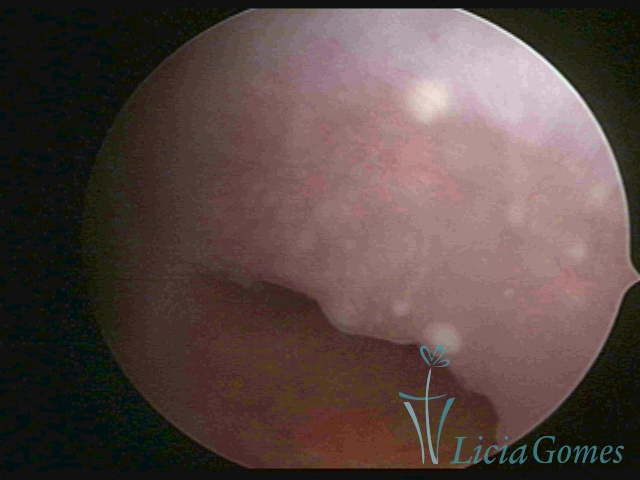

Second part or middle section

In the middle section of the cervical canal, the details of the buds are lost. It is possible to view creases and crypts. Longitudinal grooves are frequently observed. They are the most compact tissues presenting the most vascularized surface, whose vessels follow its passageway.